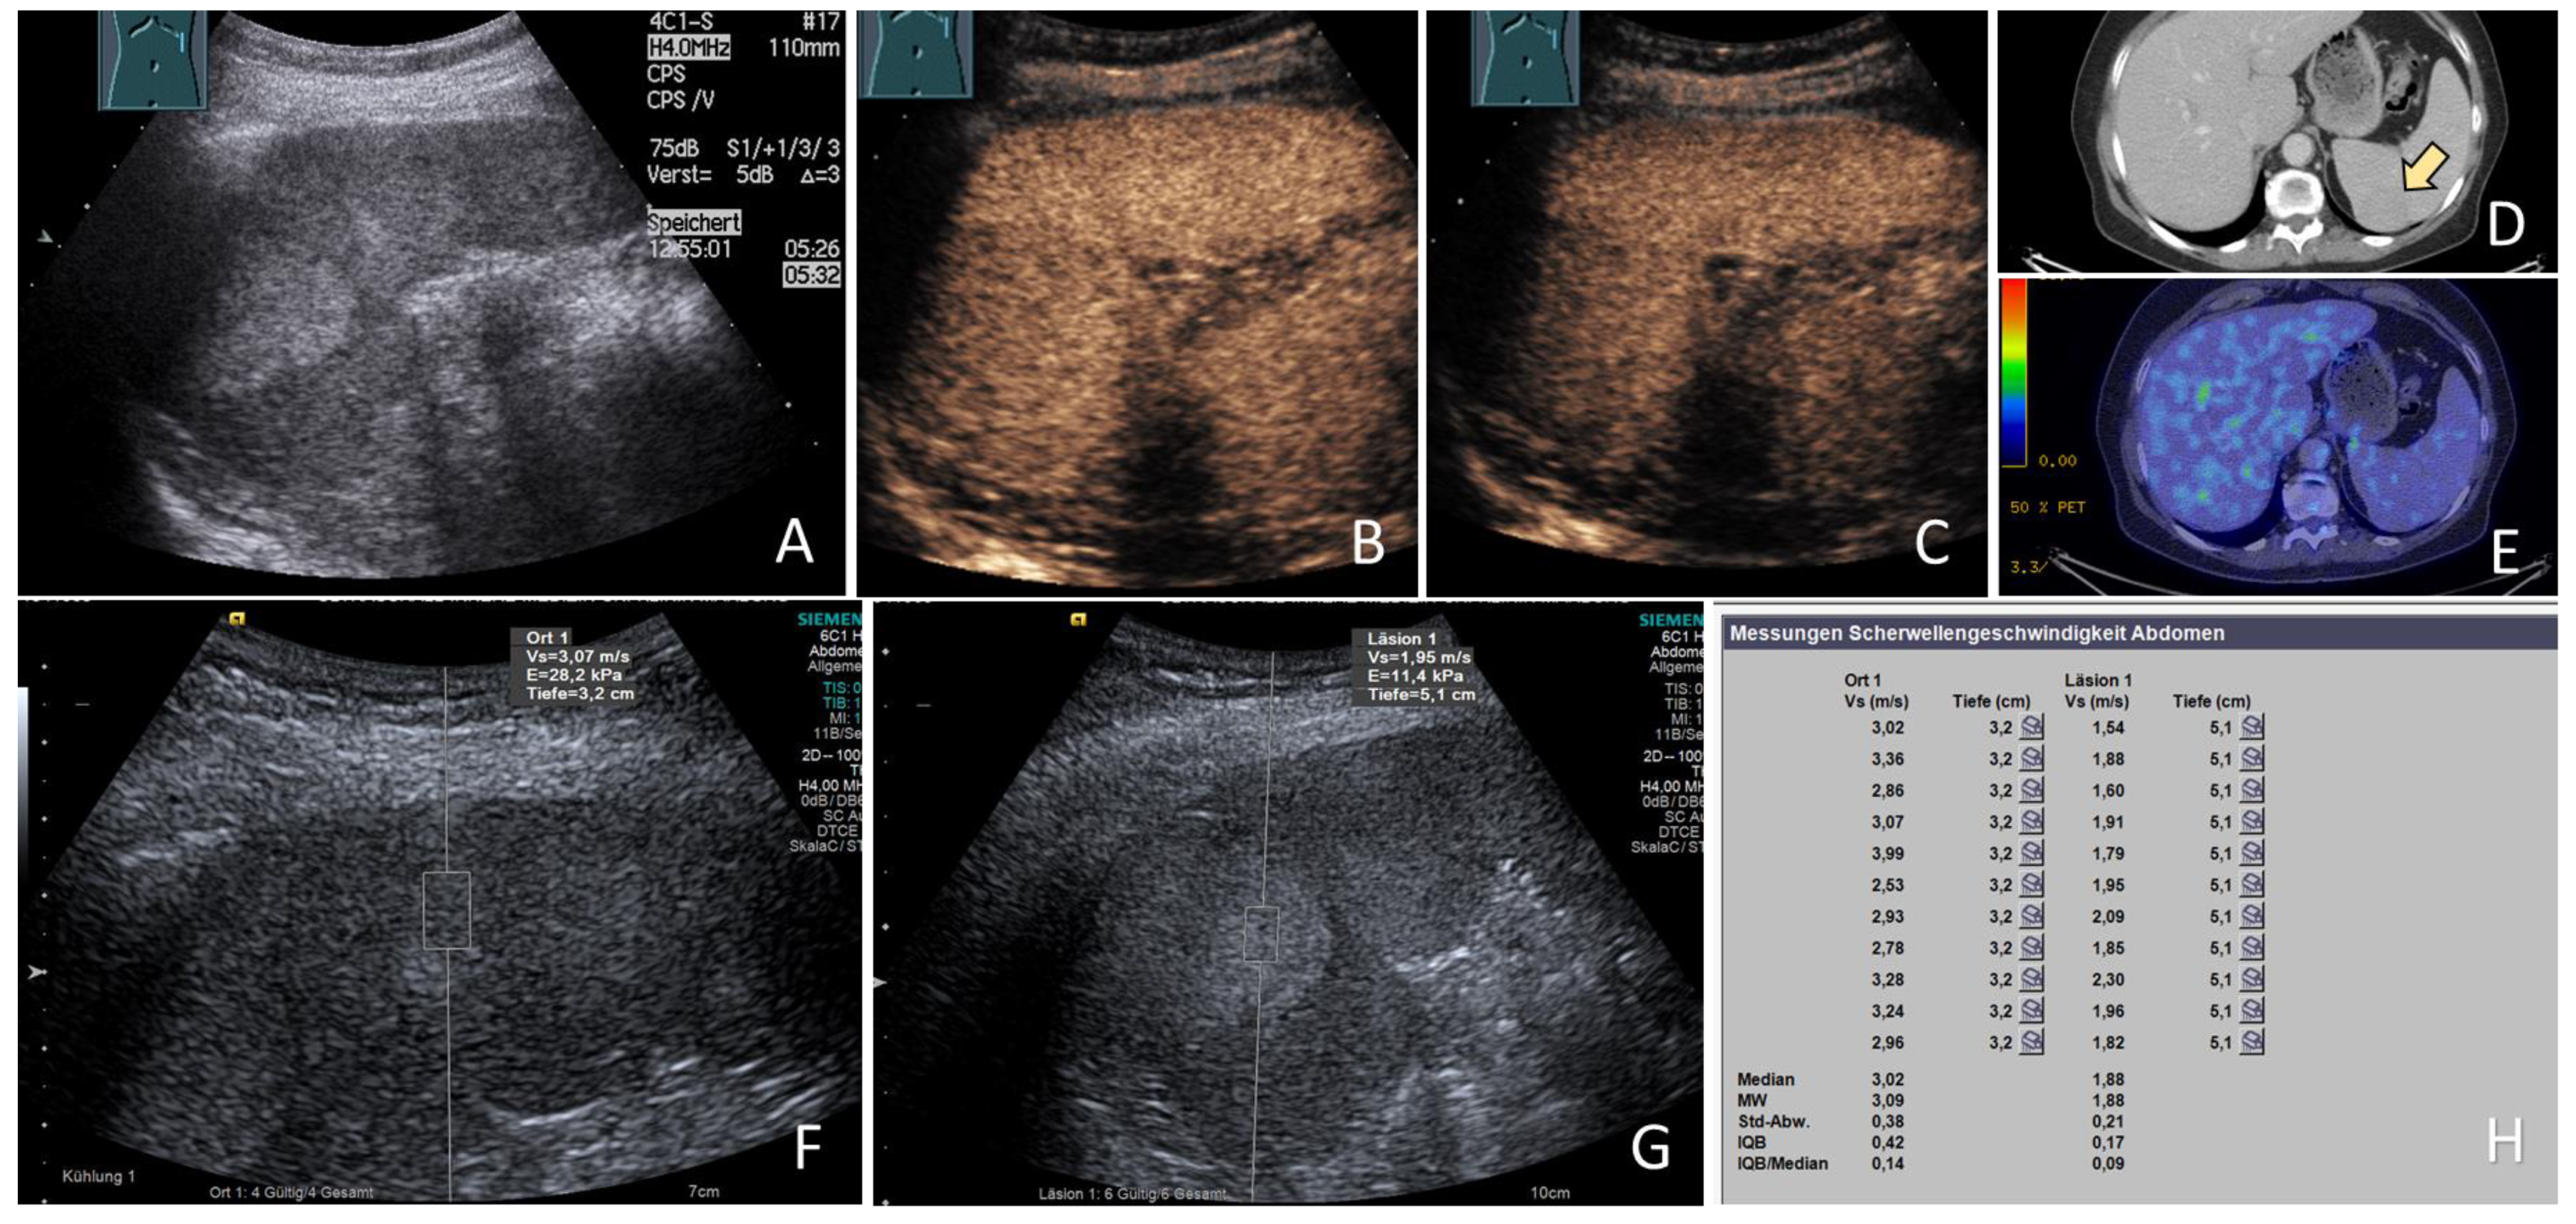

3.5. ARFI Data